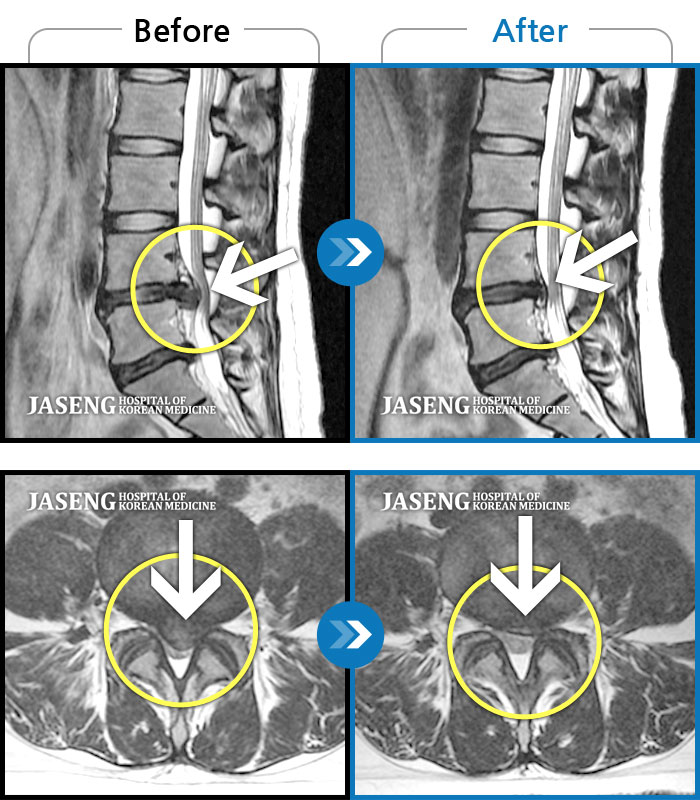

• 허리디스크